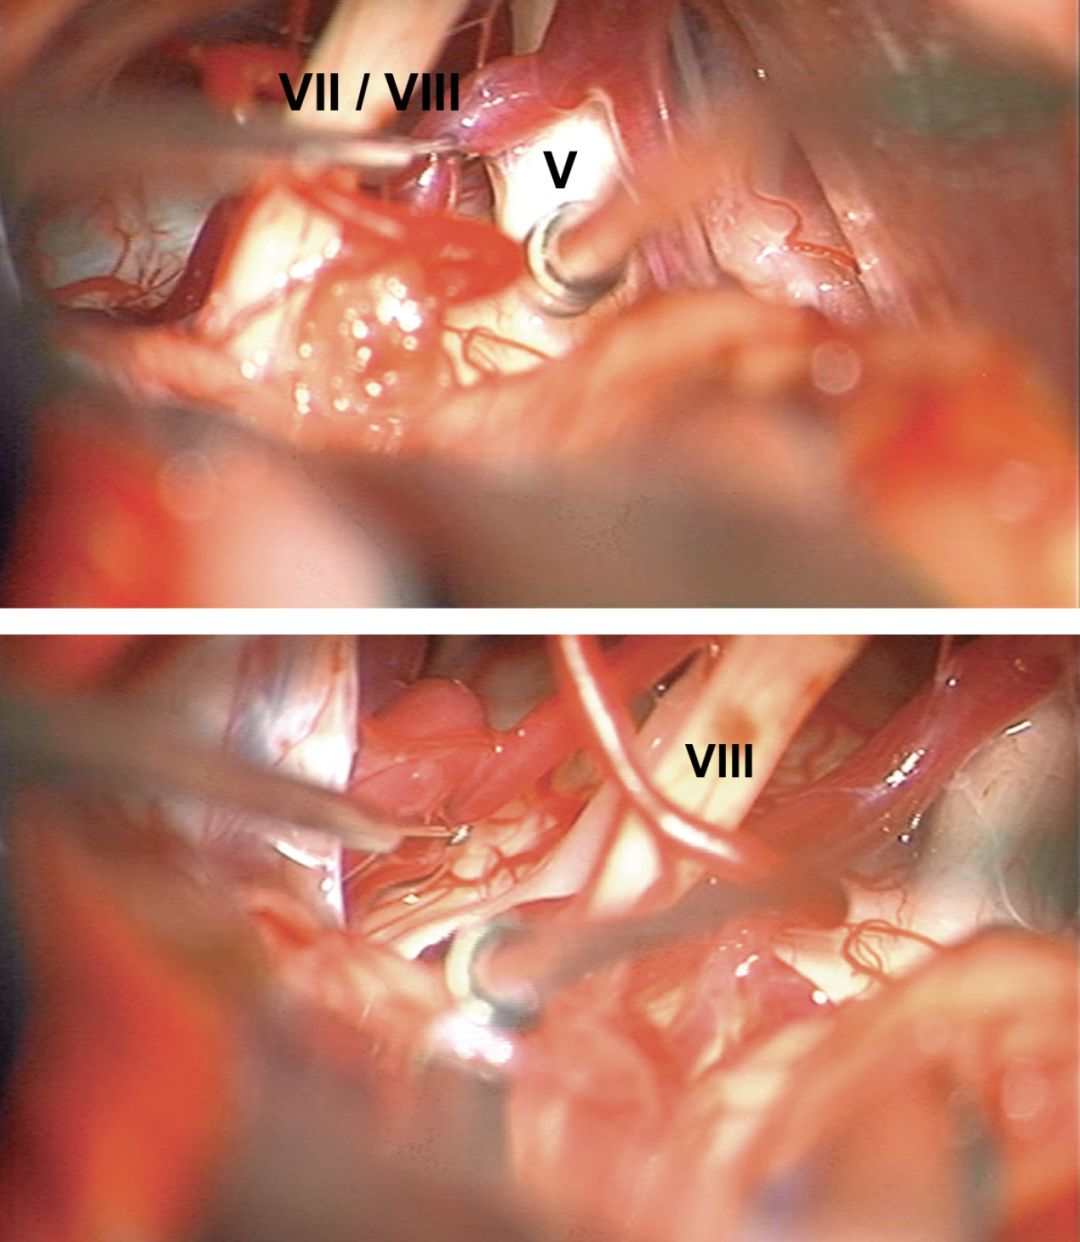

图6:暴露和探查左侧三叉神经入脑干区的术中图片(上图)。探查面听神经上、下水平的脑干以明确任何明显的血管压迫(下图)。下一步骤请看下方的图片C和D。

![]()

图7:高倍镜下用一细剥离子,小心轻柔地移动前庭蜗神经或面神经,以探查位于两者边缘的中间神经,后者应该位于前庭上神经和面神经之间。任何对前庭神经的过度操作都会大大增加术后致残性眩晕和平衡障碍的风险。

图8:大多数情况下,作者通过一尖端呈球形的细剥离子,可沿面听神经下缘,于两者之间探及中间神经。中间神经常由1~4股细支组成。蜗神经需予以听觉脑干诱发电位仔细监测。